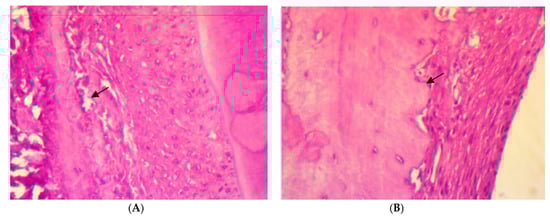

After four weeks of treatment, in SRP group, the histopathological features of the rat periodontal tissue showed the presence of a few inflammatory cells in the periodontal ligament, a moderate amount of collagen fibers, the congestion of blood vessels, fibroblast cells appearing as spindle shapes (parameter expression score of 1), and the appearance of osteoblast cells bordering the alveolar bone trabeculae. Meanwhile, in SRP+T and SRP+CU groups, no inflammatory cells infiltrations (score 0) with only blood vessels congestion, well-oriented mature collagen fibers, fibroblast cells appearing as mature spindle shapes, and strong parameter expression (score 2) could be seen, as well as osteoblast cells bordering the alveolar bone with no inflammatory cells (Figure 3).

Figure 3.

Histopathological features of rat periodontal tissue after a four-week treatment show: (A) a few inflammatory cells infiltrations in the periodontal ligament, blood vessels congestion (arrow), fibroblast cells, and osteoblasts bordering the alveolar bone trabeculae (arrow) in SRP group. (B,C) No inflammatory cells infiltrations in the periodontal ligament, mild blood vessels congestion, well-arranged collagen fibers, spindle-shaped fibroblast cells, and osteoblasts bordering the alveolar bone trabeculae (arrow) in SRP+T (B) and SRP+CU (C) groups (H&E ×400).